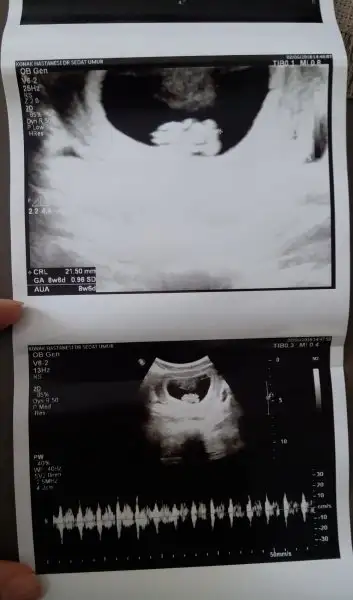

Eki Görüntüle 2153254 Merhaba bayanlar 2 oğlum var 3. Bebiş yolda 8+4 görüntü koyuyorum bana da bir tahmin yapar mısınız

HAYIRLI OLSUNN benım de 8+6 ama burda tahmn yapacak olan yok glb su sıra:) ben hıc anlamıyorum benım kese şeklı fasulye gb eger oyleyse erkek dıyorlar fasulye gb seklı ama kesenın neresınde ya bebiş çözemedim:)

Eklentiler

• CYMERA_20180602_143630.webp

11,5 KB · Görüntüleme: 178